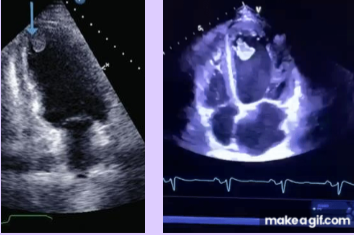

Rhabdomyoma

What is seen in this TTE?

<p>What is seen in this TTE?</p>

1. Well-circumscribed, homogenous, hyperechoic mass

2. Small, multiple lesions - may appear as thickened myocardium

Sonographic appearance of rhabdomyomas (2).

<p>Sonographic appearance of rhabdomyomas (2).</p>